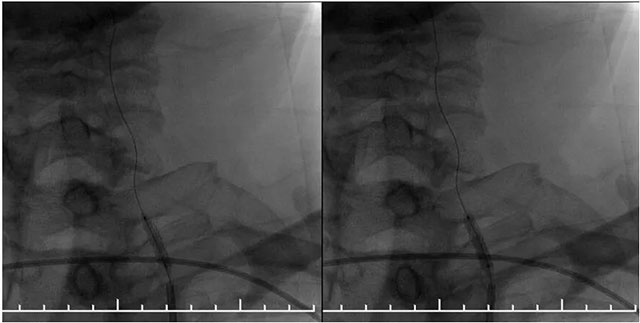

▲ DSA血管造影:左侧椎动脉支架内再狭窄

MR示双侧基底节区及右侧顶叶凸面小梗塞(部分软化灶形成)轻度脑白质疏松,MR-tof 可见左侧颈内动脉岩骨段狭窄。DSA血管造影:左侧椎动脉支架内再狭窄,左侧颈内动脉造影见岩骨段远端狭窄,右侧大脑中动脉由左侧颈内部分代偿,右侧颈动脉造影提示右侧颈内动脉闭塞。